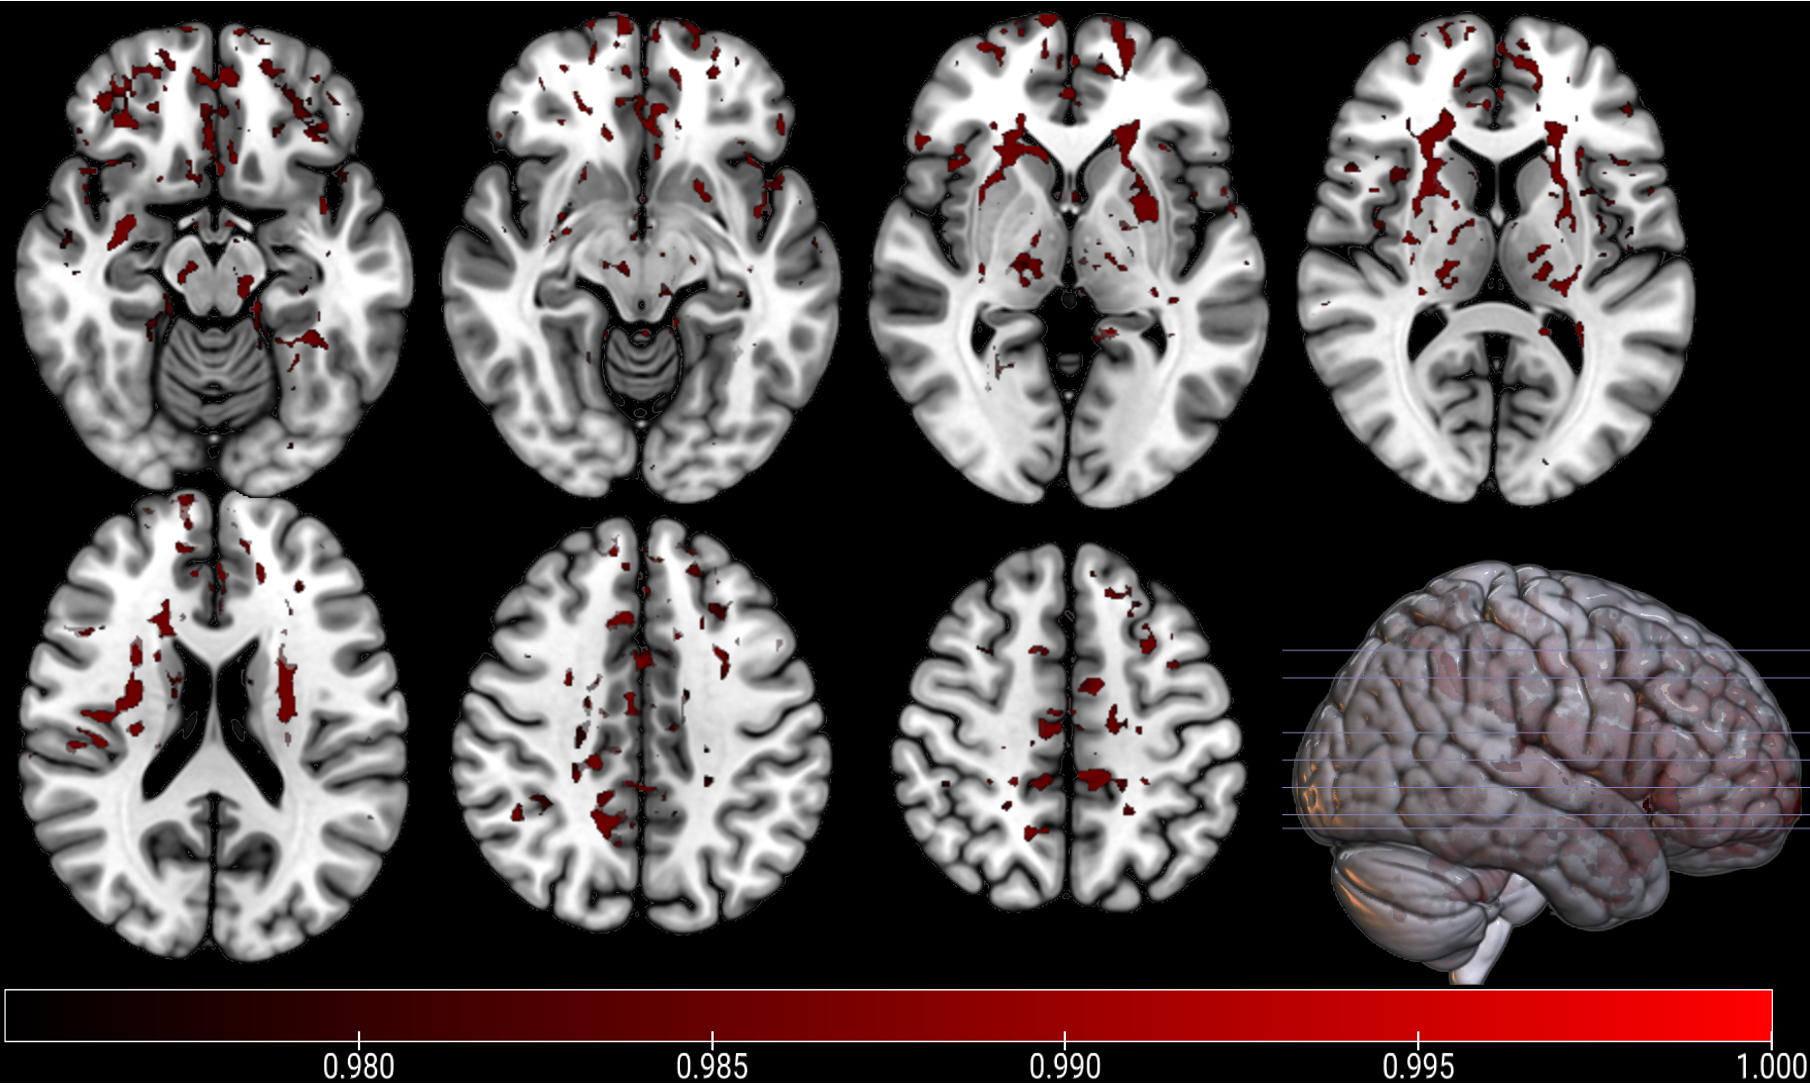

PhD candidate Athena Stein from UQ’s Child Health Research Centre, in collaboration with researchers from UQ’s Queensland Brain Institute (QBI) used Neurite Orientation Dispersion and Density Imaging (NODDI) technology.

“NODDI provides more detailed information on structural damage in the brain than traditional magnetic resonance imaging (MRI) measurements,” Ms Stein said.

“Our study was the first to use this NODDI to investigate the changes in those networks over time in children with mild traumatic brain injury.

“The children with ongoing symptoms following mild TBI had significantly lower structural integrity and more microstructural damage in their brain networks compared to the healthy controls.